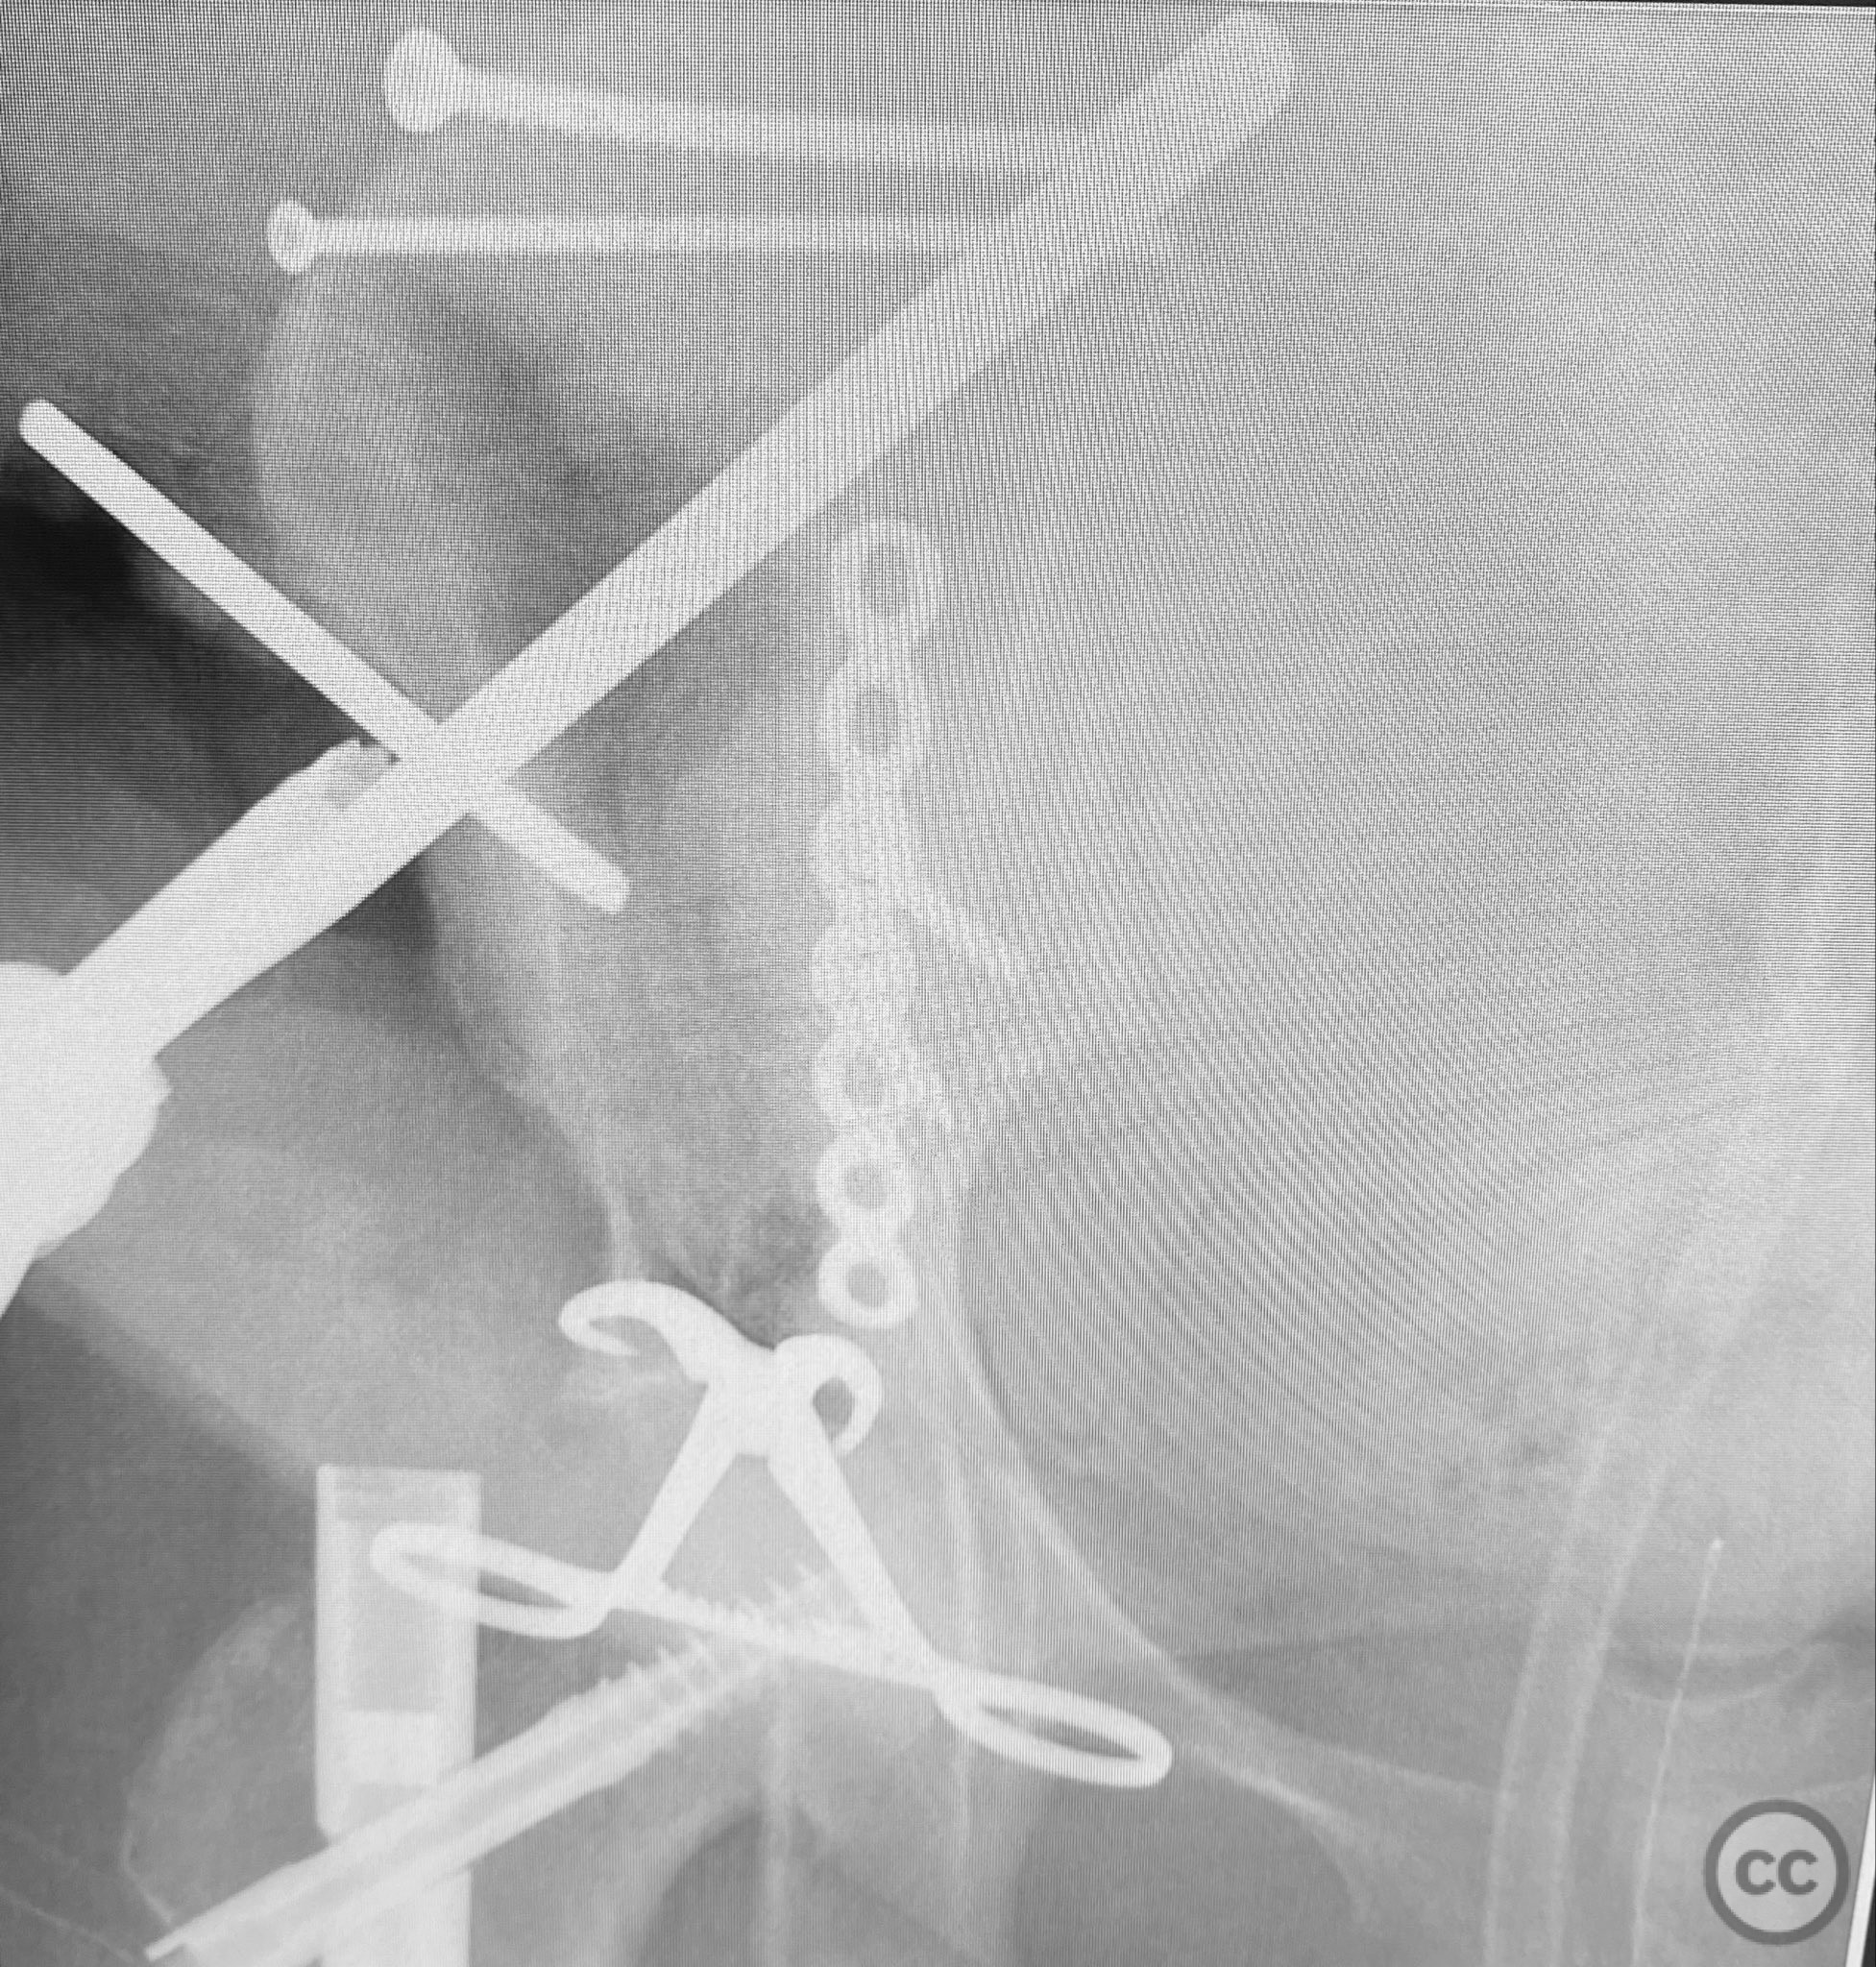

Due to significant obesity and depth of exposure, visualization of fracture surfaces required meticulous retraction and soft tissue management. Reduction was achieved using a combination of colinear clamps (applied via an iliac manipulative pin) and medium tenaculum clamps (secured through a medial bone hole). These clamps maintained reduction without obstructing subsequent implant placement. The sequence of fixation was: first, lag screws were placed across the iliac crest fracture components; second, a neutralization plate was applied along the pelvic brim with additional lag screws securing the anterior column; third, a percutaneous cannulated lag screw was inserted across the superior pubic ramus. A brim medullary screw was deliberately avoided to prevent obstruction of optimal implant placement. The plate functioned primarily as a linear washer for the lag screws rather than as a load-bearing device.

Orthopaedic implants used:   3.5mm pelvic reconstruction plate; multiple 3.5mm cortical lag screws; 6.5mm cannulated lag screw